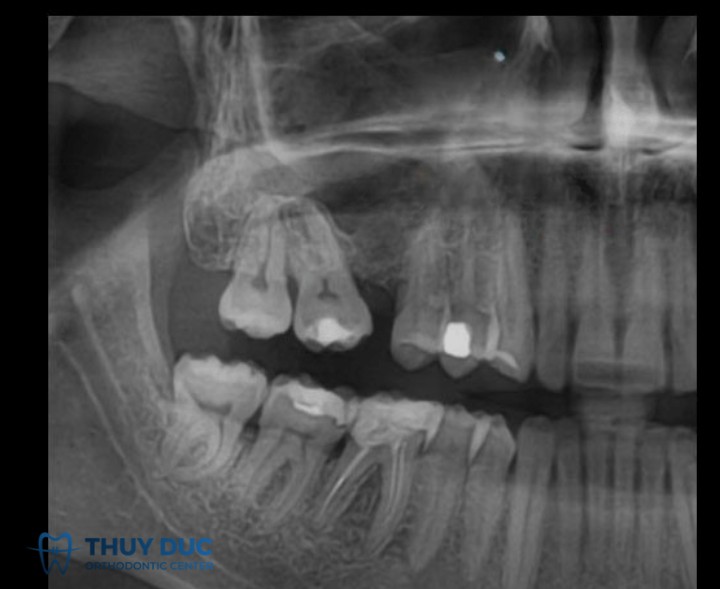

Khi một hoặc nhiều răng bị mất (do nhổ, chấn thương hoặc bệnh lý) mà không được phục hình kịp thời, các răng kế cận hai bên khoảng trống thường có xu hướng nghiêng hoặc đổ vào khoảng mất răng. Răng đối diện cũng có thể trồi xuống làm mất tương quan khớp cắn.

Một bệnh nhân mất răng hàm dưới số 6 trong thời gian dài. Răng số 5 và số 7 bị nghiêng vào khoảng trống, đồng thời răng số 6 hàm trên trồi xuống. Cần chỉnh nha để dựng trục răng 5 và 7, điều chỉnh lại răng trồi, sau đó mới phục hình bằng implant hoặc cầu răng.

- Mất răng lâu ngày: Dẫn đến tiêu xương hàm, răng nghiêng đổ nghiêm trọng.

- Xương hàm đã bị thay đổi cấu trúc: Việc di chuyển răng trên nền xương đã tiêu hoặc tái cấu trúc có thể khó khăn hơn.